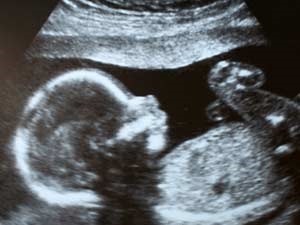

அரியானா மாநிலத்தில் உள்ள குர்கான் நகரில் இயங்கிவரும் பாட்டியா ஸ்கேன் பரிசோதனை மையத்தில் ஸ்கேன் எடுக்க வரும் பெண்களின் வயிற்றில் வளரும் கரு ஆணா?, பெண்ணா? என்ற முடிவுகள் அதிக பணம் வாங்கிக் கொண்டு தெரிவிக்கப்படுவதாக தொடர்ந்து புகார்கள் வந்தன.

இதையடுத்து, பாட்டியா ஸ்கேன் பரிசோதனை மையத்துக்கு இன்று ஒரு கர்ப்பிணி பெண்ணை அதிகாரிகள் அனுப்பி வைத்தனர். தனது வயிற்றில் வளரும் குழந்தை ஆணா?, பெண்ணா? என்று தெரிந்துகொள்ள ஆசைப்படுவதாக அந்த மையத்தின் உரிமையாளரிடம் அந்தப் பெண் கூறினார்.

பத்தாயிரம் ரூபாய் தந்தால் நீங்கள் விரும்புவது நடக்கும் என்று அந்த மையத்தின் உரிமையாளரான ராஜிவ் பாட்டியா (52) கூறியுள்ளார். அதற்கு அந்தப் பெண்ணும் சம்மதிக்க, பணத்தை பெற்றுகொண்டு ஸ்கேன் எடுத்தபோது மறைந்திருந்த அதிகாரிகள் ராஜிவ் பாட்டியாவை கையும், களவுமாக கைது செய்தனர்.